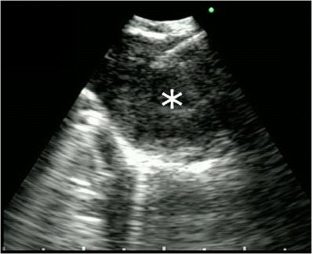

•• Wahidi MM, Herth F, Yasufuku K, Shepherd RW, Yarmus L, Chawla M, et al. Technical aspects of endobronchial ultrasound-guided transbronchial needle aspiration: CHEST guideline and expert panel report. Chest. 2016;149(3):816–35. American College of Chest Physicians Guidelines for Endobronchial Ultrasound and Transbronchial Needle Aspiration.

Yasufuku K, Pierre A, Darling G, de Perrot M, Waddell T, Johnston M, et al. A prospective controlled trial of endobronchial ultrasound-guided transbronchial needle aspiration compared with mediastinoscopy for mediastinal lymph node staging of lung cancer. J Thorac Cardiovasc Surg. 2011;142(6):1393–1400.e1.